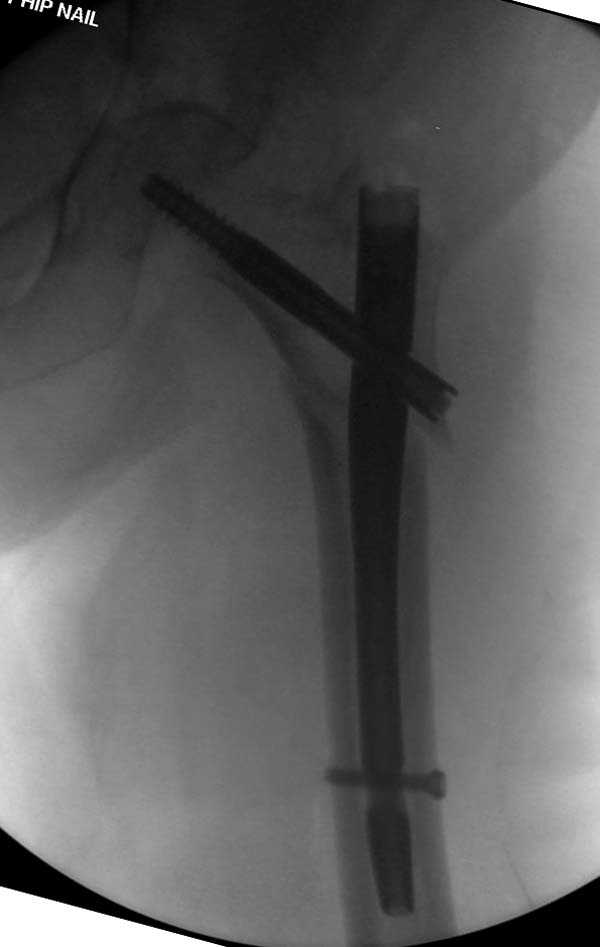

При первом послеоперационном поликлиническом осмотре больная предъявила жалобы на боли в бедре. В серийных снимках обнаружен продольный перелом верхнего отдела бедра.

Считаем, что техническая ошибка произошла во время установки гвоздя, когда рассверливанию канала не уделили должного внимания. Канал остался узковат, и гвоздь был забит с силой. Полная нагрузка конечности приостановлена на две недели, и боли в конечности изчезли. Больная начала нагрузку и перелом срастается.-- Djoldas Kuldjanov, M.D.Associate ProfessorDepartment of Orthopedic SurgerySt. Louis University

I have a different interpretation of this case. I suspect you did not tighten the set screw all the way in order to allow sliding of the lag screw and fracture fragment compression, as you would for a standard intertrochanteric hip fracture. This is a reverse obliquity fracture, so the result is migration of the proximal segment. I doubt reaming the canal would have prevented this. Had the set screw been fully tightened, there would be no postoperative fragment motion.

I looked at the films again and saw that you are referring to the nondisplaced shaft fracture, not the proximal fragment position. Sorry.

Мне думается, что варусное положение проксимального отломка на последующих снимках не более чем проекционный феномен. Раскол же диафиза вдоль, наверняка, связан с чрезмерно насильственным введением штифта. Вообще, при реверсивных, да и обычных вертельных переломах, многие давно отказались от короткой Гаммы в пользу long-версии. Но в любом случае надо быть на 100 уверенным в подготовке канала.